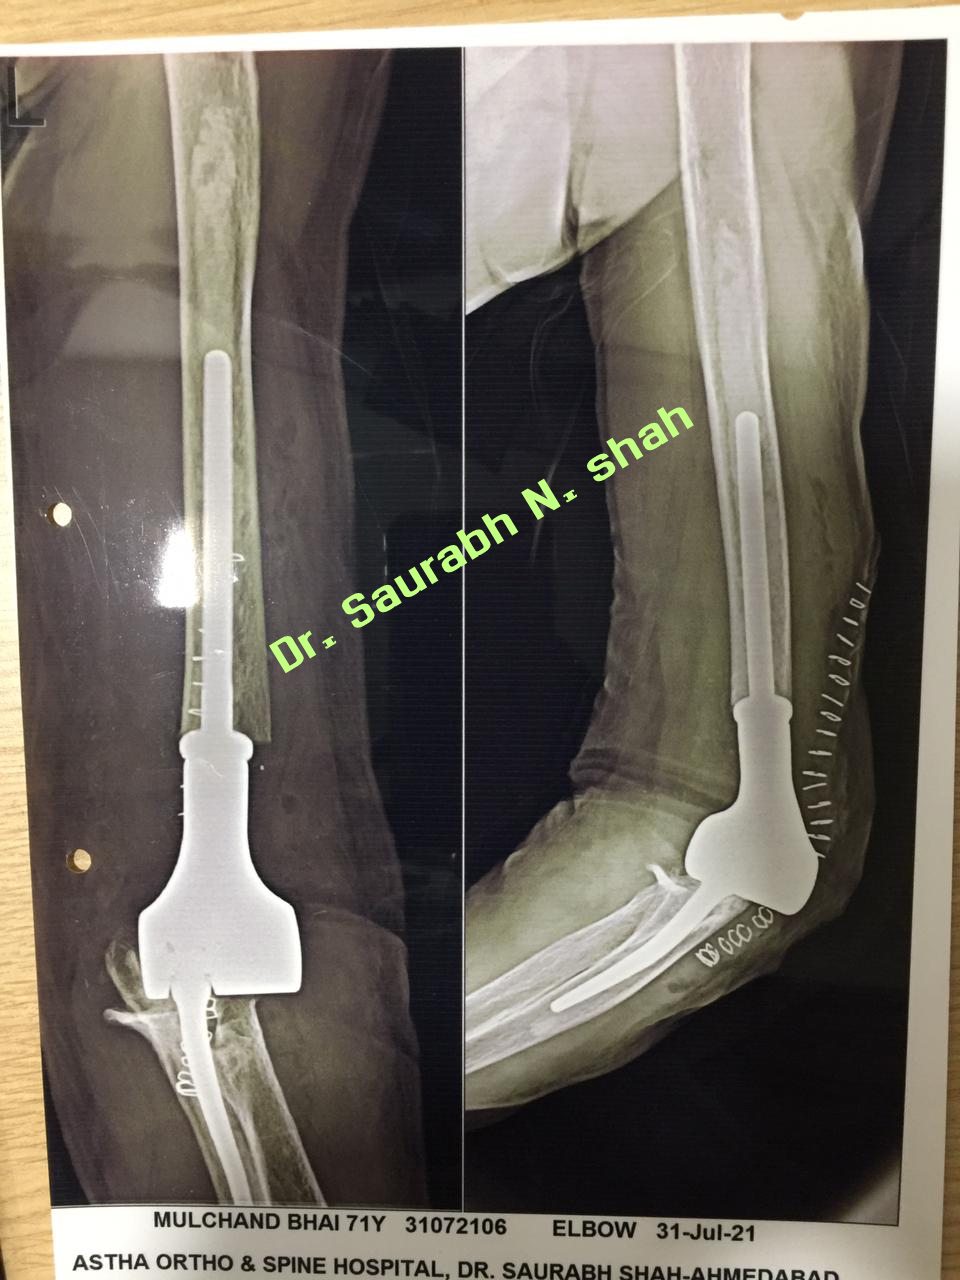

Elbow Joint Replacement